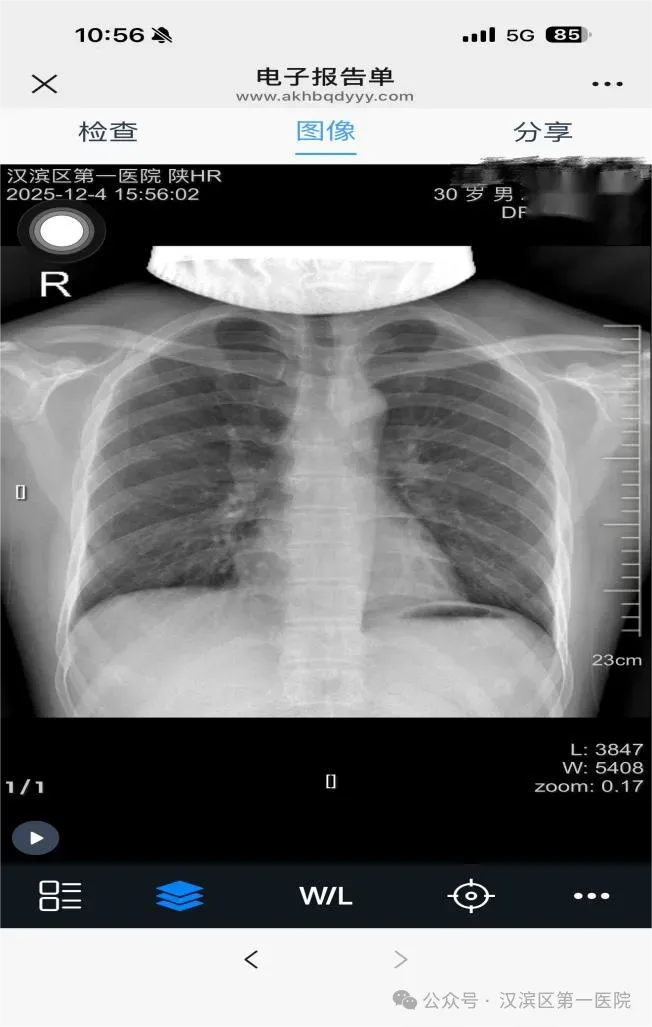

“云胶片”是一种基于互联网和云存储的医学影像服务。您完成X光、CT、MR等检查后,影像资料和报告将自动加密上传至安全云端,生成一个专属的二维码。您只需一部手机,即可随时随地查看、下载自己的原始影像和报告,就像在手机里建了一个终身可查的私人影像档案库。

打开微信,扫描二维码,完成身份信息验证后,即可查询您的相关报告。

查看与管理

浏览您的影像资料和诊断报告。